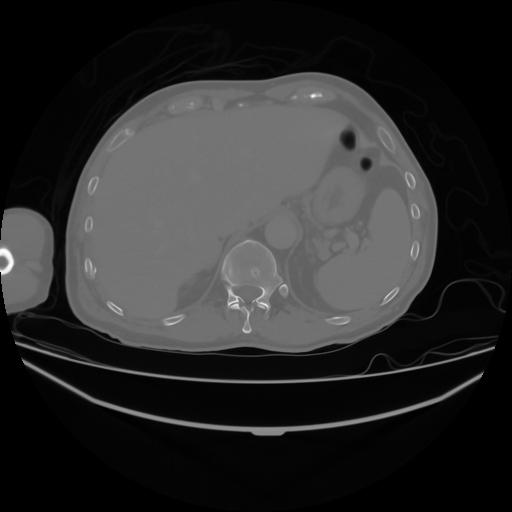

4 CUERPO,CE,Axial,3.0,CUERPO,,